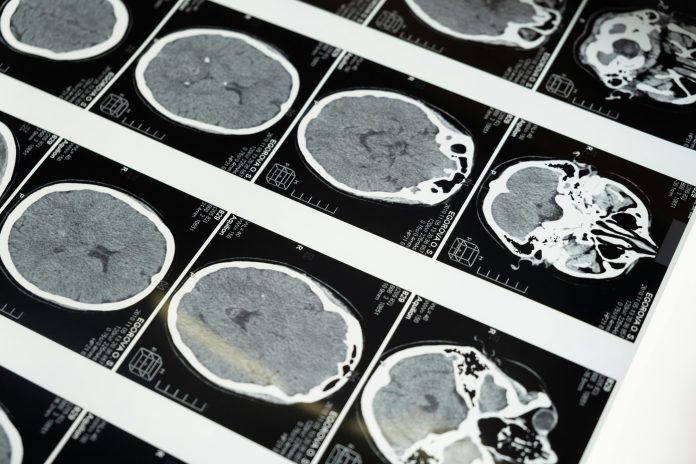

Dr Patty Francis, President of the Neurological Association of South Africa, says dementia is often the result of decades of exposure to modifiable risk factors that result in brain tissue damage. They include:

Common warning signs include memory loss, confusion, personality changes, difficulty completing everyday tasks, and problems with speech or coordination.